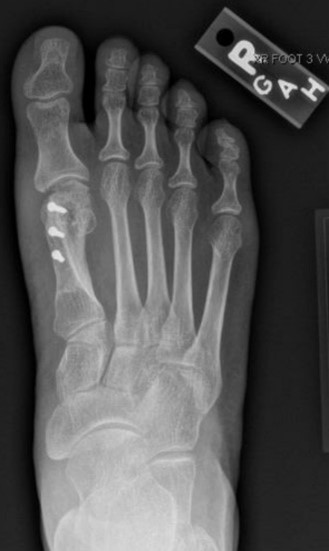

Hallux valgus-bunion deformity

Figure 1: Hallux valgus (bunion deformity)

A bunion, also known as hallux valgus, is a bony prominence at the base of the big toe, which often results in pain, redness, and rubbing in footwear. The 1st metatarsal bone abnormally angles outward towards the other foot from its joint in the midfoot. A bunion can change the shape of your foot, make it difficult for you to find shoes that fit correctly, and worsen the symptoms if left untreated.

The diagnosis of a bunion includes taking a medical history and performing a physical examination to assess the extent of misalignment and damage to the soft tissues. Weight-bearing X-rays are taken while standing to assess the severity of the bunion and deformity of the toe joints.